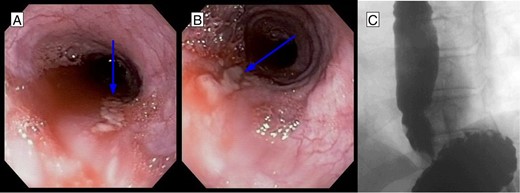

An 81-year-old male presented to the emergency department with hematemesis and epigastric pain. On the evening of presentation, the patient reported difficulty in swallowing a piece of meat during dinner, which led to several episodes of retching followed by bloody emesis. His medical history was significant for extensive cardiovascular diseases including hypertension, stroke and pulmonary embolism for which an inferior vena cava filter had been in place. He had also undergone a carotid endarterectomy and taking daily aspirin. On initial presentation, the patient was afebrile, in sinus rhythm and normotensive. He had several episodes of hematemesis in the emergency department, and a nasogastric tube was placed with 500 ml of sanguineous output. Chest examination did not reveal any subcutaneous air, and lungs were clear bilaterally. On abdominal exam, however, the patient had tenderness to deep palpation of the epigastrium without any signs of peritonitis. Laboratories were significant for leukocytosis to 16.5 × 109/l and hemoglobin of 11.6 × 109/l. A computed tomography (CT) scan of the abdomen and pelvis with oral contrast was performed, which showed extraluminal contrast extending around the esophagus and around the left crus of the diaphragm that was compatible with esophageal perforation (Fig. 1A). The patient was resuscitated with fluids, started on broad spectrum antibiotics and after reviewing the CT scan was taken to the operating room for endoscopy, which revealed a 7-cm long esophageal perforation, starting at 29 cm and covered with blood clot. The gastroesophageal junction was identified at 42 cm from the incisors. About 1 l of blood was suctioned from the stomach and the GE junction was again visualized in retrograde view for possible involvement. There was no evidence of a tear in the gastric wall and no active bleeding was visualized. A partially covered self-expanding metal WallFlex stent (Boston Scientific) was introduced over a wire into the esophagus and deployed, covering the entire length of the perforation (Fig. 1B). The stent was bridled in place with an umbilical tape and we proceeded with an exploratory laparoscopy, which did not reveal any evidence of purulence near the area of the hiatus. A laparoscopic feeding jejunostomy tube was also placed at the time. Postoperative course was uneventful. The patient was kept nil per os for the next month, on tube feeds and antibiotics. His leukocytosis resolved over the ensuing days and his hemoglobin remained stable. A month later he presented to the hospital for esophageal stent removal. After endoscopically removing the stent, small healing ulcerations were identified in the area of previous perforation (Fig. 2A and B). An esophagram was performed using water soluble Omnipaque contrast to evaluate for a possible leak at the ulceration sites; however, no frank leak was found (Fig. 2C). The patient was then started on a clear liquid diet and discharged home. He was slowly advanced to a regular diet over the next several weeks which he tolerated well without any further complications.

(A, B) EGD after stent removal revealed small healing lacerations in the area of previous perforation. (C) Follow-up esophagram without evidence of leak of contrast.